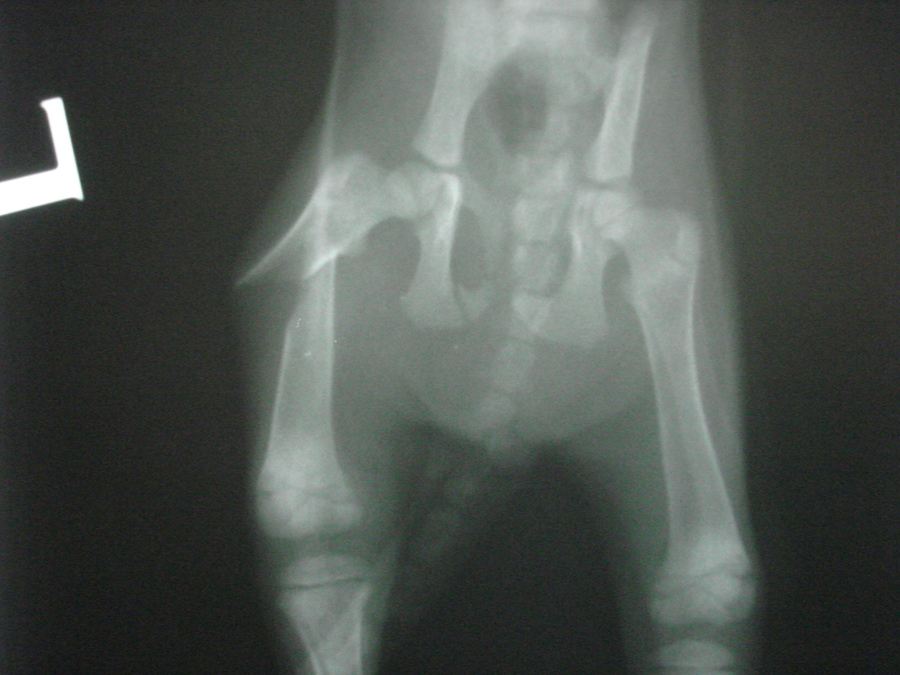

Vzhledem k tomu, že se jednalo o kompletní šikmou dislokovanou zlomeninu stehenní kosti, bylo po stabilizaci kotěte přikročeno k chirurgickému řešení zlomeniny. To spočívalo v anatomické repozici fragmentů stehenní kosti a k jejich fixaci pomoci nitrodřeňového hřebu a dvou cerkláží tenkým chirurgickým drátem zajišťující stabilitu fragmentů po operaci.

Fraktura stehenní kosti kotěte po operaci2

Fraktura stehenní kosti kotěte po operaci1